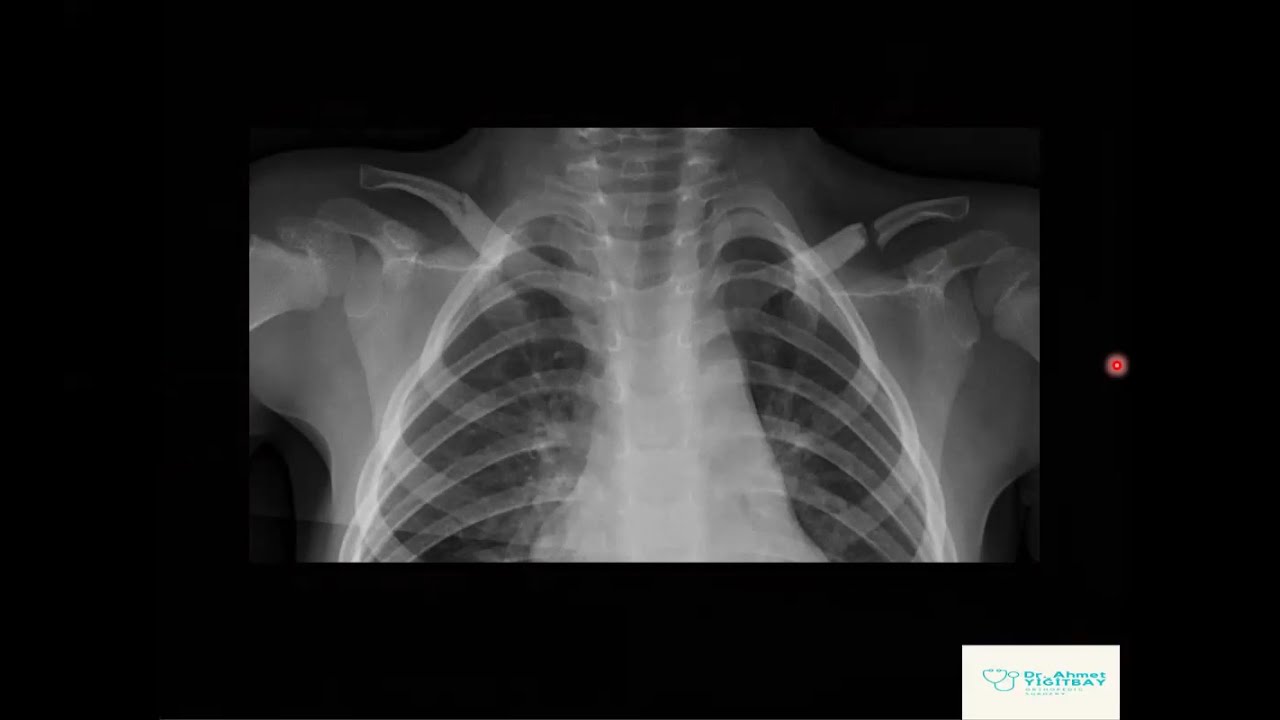

• AKCİĞER GRAFİSİ YORUMLAMA

AKCİĞER GRAFİSİ YORUMLAMA